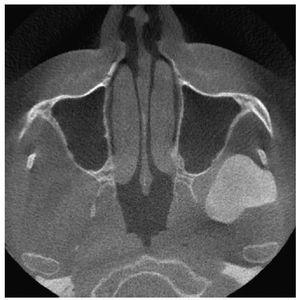

La radiografía panorámica (fig. 1) mostró una estructura de tejido óseo, densa, homogénea, con forma de hongo, bordes bien definidos y un diámetro de varios centímetros. La lesión parecía originarse en un área por encima del agujero mandibular. Un TAC de haz de cono (figs. 2 a 5) reveló la presencia de una lesión homogénea osteodensa de 3 x 3 x 2,7 cm que crecía a partir de un pedúnculo en la cara lingual de la escotadura mandibular. La circunferencia anterior alcanzaba casi a la apófisis coronoides.

Figura 2. Imagen axial de un TAC de haz de cono.